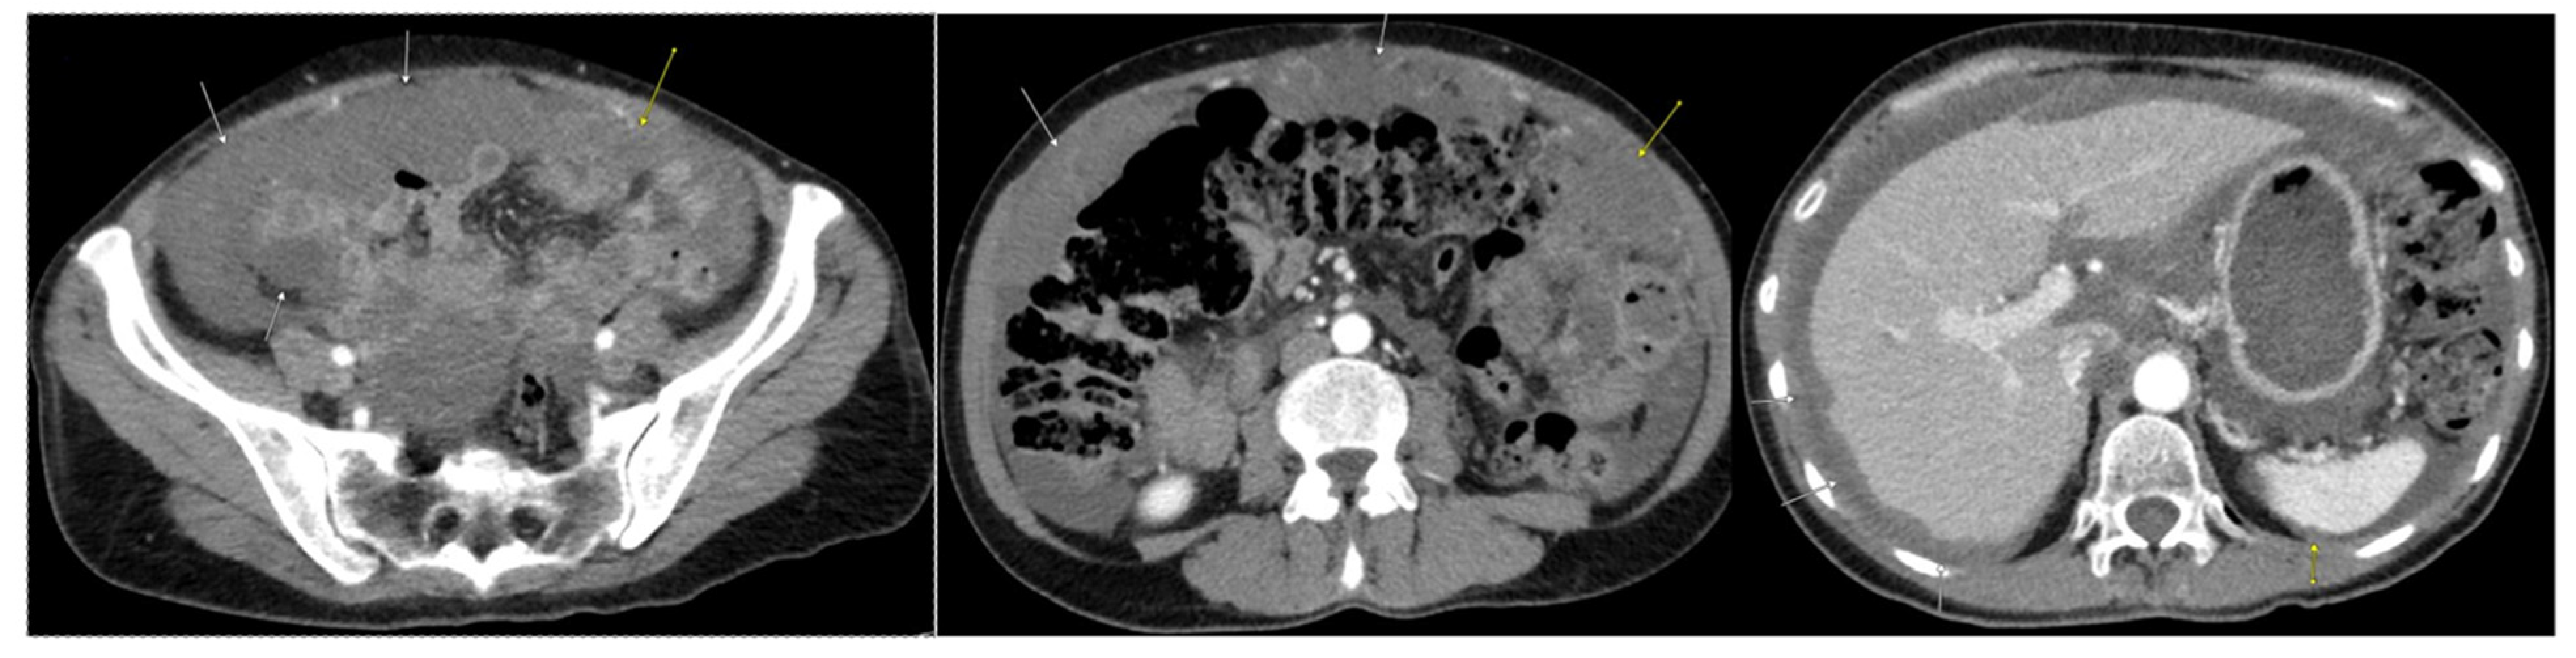

2. Case